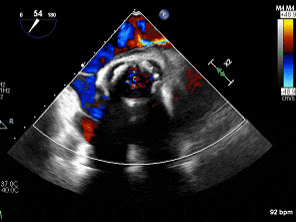

术后主动脉瓣生物瓣无瓣周漏

(食道中段主动脉瓣短轴切面)